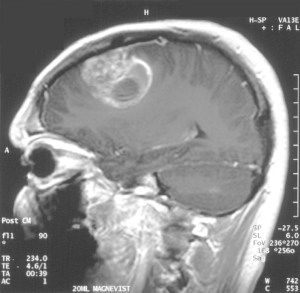

The patient is a 50-year-old man named Richard Grady who was participating in an investigational clinical trial run out of the City of Hope’s CIRM Alpha Stem Cell Clinic. A brain scan revealed a brightly lit tumor on the right side of Richard’s brain. Doctors surgically removed the tumor and treated him with radiation in an attempt to staunch further growth. But after six months, the tumors came back with a vengeance, spreading to other parts of his brain, lighting up his MRI scan like a Christmas tree.

In Richard’s case, CAR-T cells were first infused into his brain through a tube in an area where a tumor was recently removed. No new tumors grew in that location of his brain, but tumors in other areas continued to grow and spread to his spinal cord. At this point, the scientists decided to place a second tube into a cavity of the brain called the ventricles, which contain a clear liquid called cerebrospinal fluid. Directly infusing into the spinal fluid allowed the cancer fighting cells to travel to different parts of the brain and spinal cord to attack the tumors.

Three infusions of the CAR T-cell treatment shrunk Richard’s tumors noticeably, and a total of ten infusions was enough to melt away Richard’s tumors completely. Amazingly, Richard was able to reduce his medications and go back to work.

CAR T-cell therapy reduces brain tumors when infused into the spinal fluid. (NEJM)